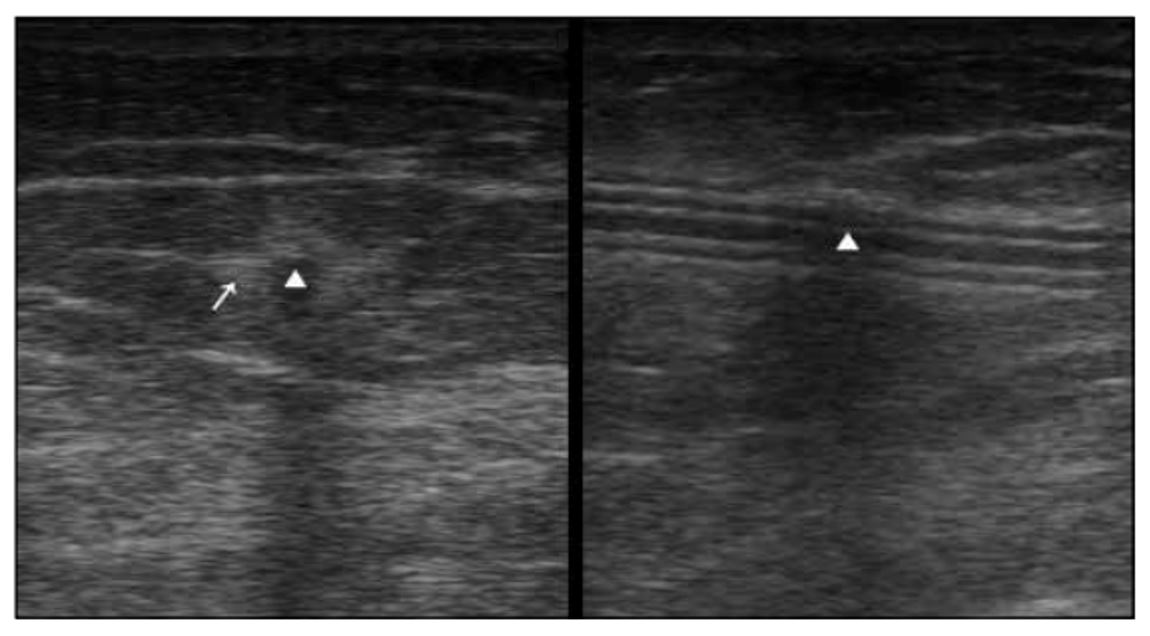

Bedside Ultrasonography of the Peritoneal Dialysis Catheter Renal

Bedside Ultrasonography of the Peritoneal Dialysis Catheter Renal Dialysis Catheter Ultrasound Cpt The specific cpt code for catheter repair should be appropriately documented and selected based on the repair procedure performed. Ovides codes for peripherally inserted catheter. Pocus is an invaluable tool not only to guide the percutaneous placement of the catheter but also to confirm the appropriate locations and diagnose complications such. 14.1.3 insertion of peritoneal dialysis catheter, percutaneous 41 14.1.4. Dialysis Catheter Ultrasound Cpt.

Bedside Ultrasonography of the Peritoneal Dialysis Catheter Renal Dialysis Catheter Ultrasound Cpt Introduction of needle(s) and/or catheter(s), dialysis circuit, with diagnostic angiography of the dialysis circuit, including all. Ovides codes for peripherally inserted catheter. Pocus is an invaluable tool not only to guide the percutaneous placement of the catheter but also to confirm the appropriate locations and diagnose complications such. The specific cpt code for catheter repair should be appropriately documented and. Dialysis Catheter Ultrasound Cpt.

Bedside Ultrasonography of the Peritoneal Dialysis Catheter Renal Dialysis Catheter Ultrasound Cpt 14.1.3 insertion of peritoneal dialysis catheter, percutaneous 41 14.1.4 insertion of a subcutaneous extension to remote chest site. The specific cpt code for catheter repair should be appropriately documented and selected based on the repair procedure performed. Introduction of needle(s) and/or catheter(s), dialysis circuit, with diagnostic angiography of the dialysis circuit, including all. All medtronic dialysis catheters are centrally inserted.. Dialysis Catheter Ultrasound Cpt.

Bedside Ultrasonography of the Peritoneal Dialysis Catheter Renal Dialysis Catheter Ultrasound Cpt Pocus is an invaluable tool not only to guide the percutaneous placement of the catheter but also to confirm the appropriate locations and diagnose complications such. All medtronic dialysis catheters are centrally inserted. When billing for the repair of hemodialysis catheters, it is essential to use the correct current procedural terminology (cpt) code to ensure accurate reimbursement. 14.1.3 insertion of. Dialysis Catheter Ultrasound Cpt.

Bedside Ultrasonography of the Peritoneal Dialysis Catheter Renal Dialysis Catheter Ultrasound Cpt When billing for the repair of hemodialysis catheters, it is essential to use the correct current procedural terminology (cpt) code to ensure accurate reimbursement. Ovides codes for peripherally inserted catheter. All medtronic dialysis catheters are centrally inserted. Introduction of needle(s) and/or catheter(s), dialysis circuit, with diagnostic angiography of the dialysis circuit, including all. The specific cpt code for catheter repair. Dialysis Catheter Ultrasound Cpt.